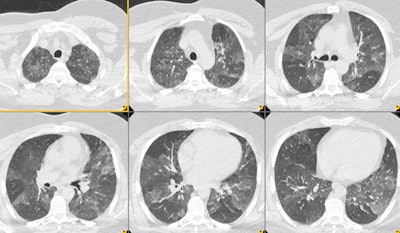

Mosaic attenuation due to air trapping:

Inspiratory CT demonstrated mosaiform attenuation to the lung parenchyma. On expiration, areas of decreased attenuation persisted which confirmed air trapping as the etiology of the mosaiform attenuation in this patient.

Inspiration:

Expiration:.